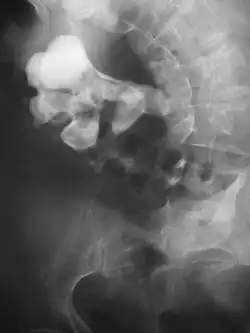

Radiograph showing a large staghorn calculus involving the major calyces and renal pelvis in a person with severe scoliosis

Stones less than 5 mm (0.2 in) in diameter pass spontaneously in up to 98% of cases, while those measuring 5 to 10 mm (0.2 to 0.4 in) in diameter pass spontaneously in less than 53% of cases.[85]

Stones that are large enough to fill out the renal calyces are called staghorn stones and are composed of struvite in a vast majority of cases, which forms only in the presence of urease-forming bacteria. Other forms that can possibly grow to become staghorn stones are those composed of cystine, calcium oxalate monohydrate, and uric acid.[86]